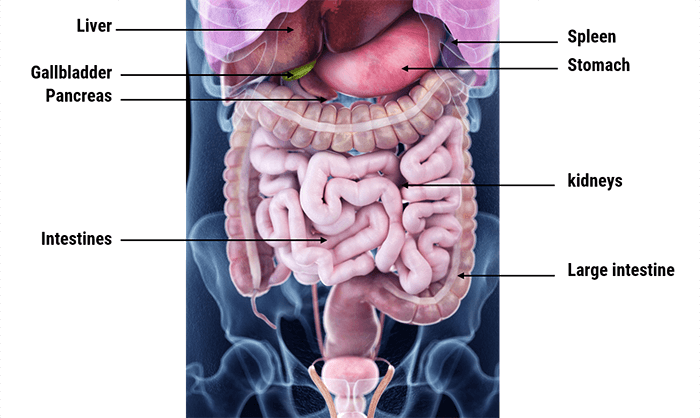

The abdominal cavity is the largest body cavity in humans, it is lined by a thin, serous membrane called the peritoneum and contains different vital organs such as the liver, gallbladder, stomach, spleen, pancreas, kidneys, ureters, intestines, and the arterial and venous systems.

The stomach is a thick-walled digestive organ found on the left side of the abdomen. It is followed by the first portion of the small intestine, called the duodenum.

The Liver is the largest organ in the abdomen. It is located on the upper right side of it, right under the diaphragm. It has two lobes that are separated by a ligament. It plays a crucial role in our bodies as it maintains normal blood glucose levels, produces bile, and detoxifies the blood.

The Gall bladder is found below the liver and is connected to it. It stores and concentrates bile that is sent to the duodenum when needed for fat digestion and absorption.

The spleen is part of the immune system. Its functions include taking part in the production of white blood cells, storing platelets, and destroying dead red blood cells and harmful substances.

The Pancreas is a part of the digestive system, it produces important digestive enzymes, as well as insulin and glucagon, which are crucial for the metabolism of carbohydrates in our bodies.

The small intestine is found between the stomach and large intestine and is made up of three parts: the duodenum, jejunum, and ileum. It is a long, tube-shaped digestive organ, where digestion and absorption of nutrients take place.

The large intestine is the organ to which undigested material is sent. It is U-shaped and is made up of the cecum, colon, rectum, canal, and appendix. Absorption of water and electrolytes and the formation of feces all occur here.

The two kidneys are found on either side of the abdomen. They play an essential role in the body, because they ensure the detoxification of the blood, the creation of urine, and the maintenance of water and acid balance in the body. Attached to each kidney are tubes, called the ureters, which connect them to the urinary bladder. In addition to the kidneys’ functions, the adrenal glands found on the kidneys produce important hormones, such as norepinephrine and ADH.